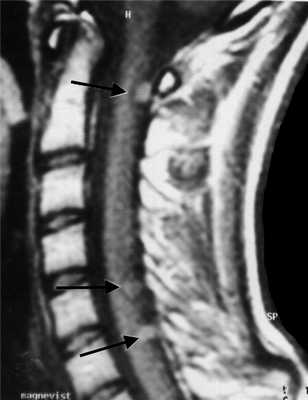

МРТ шейного отдела позвоночника. Нейрофиброматоз тип II. Множественные невриномы (стрелки). Т1-взвешенная МРТ с контрастированием.

МРТ шейного отдела позвоночника. Лептоменингеальные метастазы (стрелки). Сагиттальная Т1-взвешенная МРТ с контрастированием.